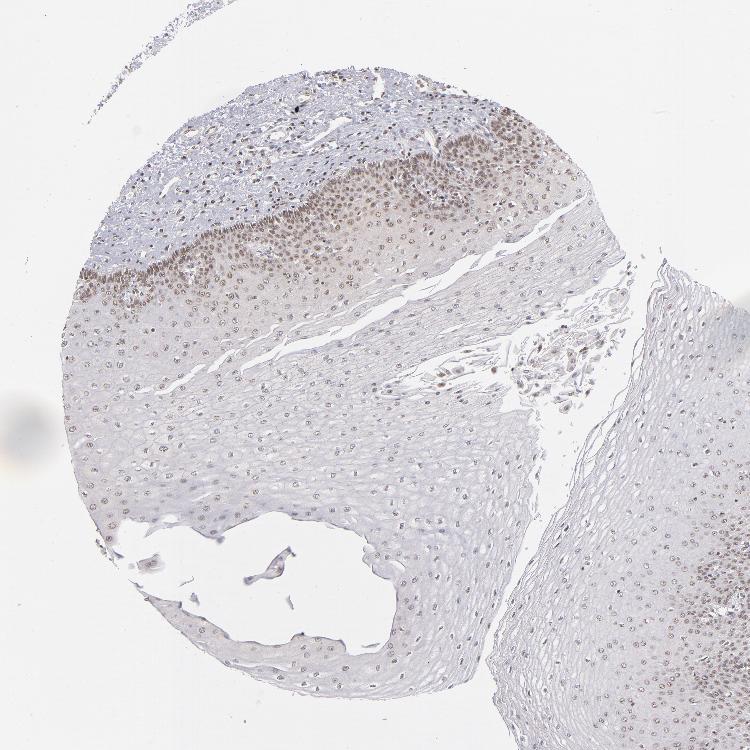

ESOPHAGUS - Antibody stainingi

Antibody staining in the annotated cell types in the current human tissue is reported as not detected, low, medium, or high, based on conventional immunohistochemistry profiling in selected tissues. This score is based on the combination of the staining intensity and fraction of stained cells.

Each image is clickable and will lead to virtual microscopy that enables deeper exploration of all samples and also displays staining intensity scores, fraction scores and subcellular localization as well as patient and tissue information for each sample.

Antibody HPA001824

Squamous epithelial cells Medium